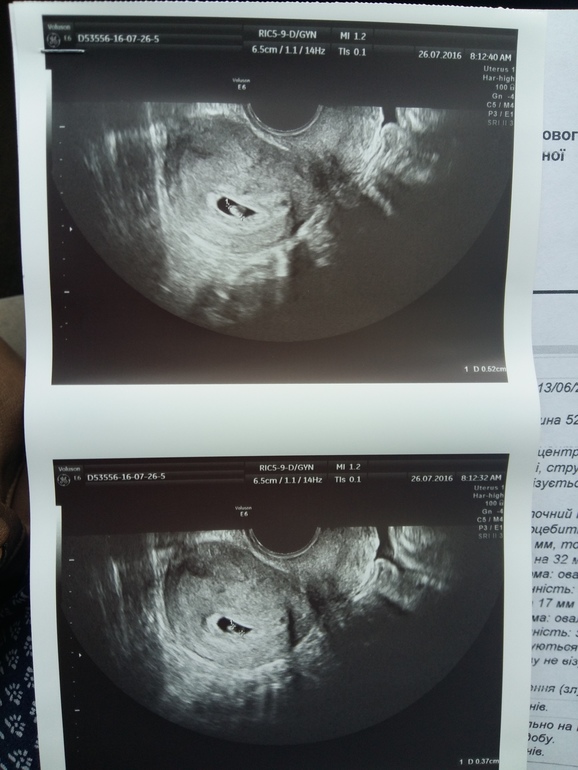

Ну и что скажете, я думаю ну все не дай Бог внематочная, у всех такие цифры бешенные, и тесты яркие(( Ладно бегу на 12 ДПП сдаю опять ХГЧ. При этом месячные не начались, живот все так же ноет. И все. Приходит результат - 139! Ну блин, ну растет но все таки мало. Делаю тест, который дороже, чувствительность от 5 МО, и там полоска еще бледнее, я его даже не фоткала, потому что думала, все ясно(( Ну и на 14 дпп сдаю тест - и там 421)) Вот и все ясно. Растет малыш. Больше я тестов не делала, и делать не собираюсь. Позвонила врачу - он сказал 26.07 на узи, все без изменений утрик и фольку. И пошли дико длинные недели ожиданий. А живот болит, и сильно так временами. Как скрутит, или спазм или в боку. Я в панике немного была, но держала себя в руках. Пила 2 но-шпы в день, когда совсем не в моготу, и все. Хочу сказать, что сильней всего живот ныл в дни предполагаемых М, и потом еще дня 3. В прошлый вторник позвонила врачу и говорю живот побаливает, он папаверин вам в помощь. Ну я пошла его купила, но так ни разу и не поставила. Буквально на след день, живот стал нормальным)) Видать испугался. А я против всяких препаратов без необходимости. И вот сегодня, в 9:00 утра пошли мы на уз с мужем, и там, девочки, там малыш, один, крепыш, сердечко стучит, КТР есть, плодное яйцо и желточный мешочек есть, все в норме соответствует 6 неделям. Я БЕРЕМЕННА!!! Я счастлива, слушали сердечко, чуть не расплакались с мужем. Теперь на учет в 8 недель вставать. Вот такая история.

Мой красавчик или красавица